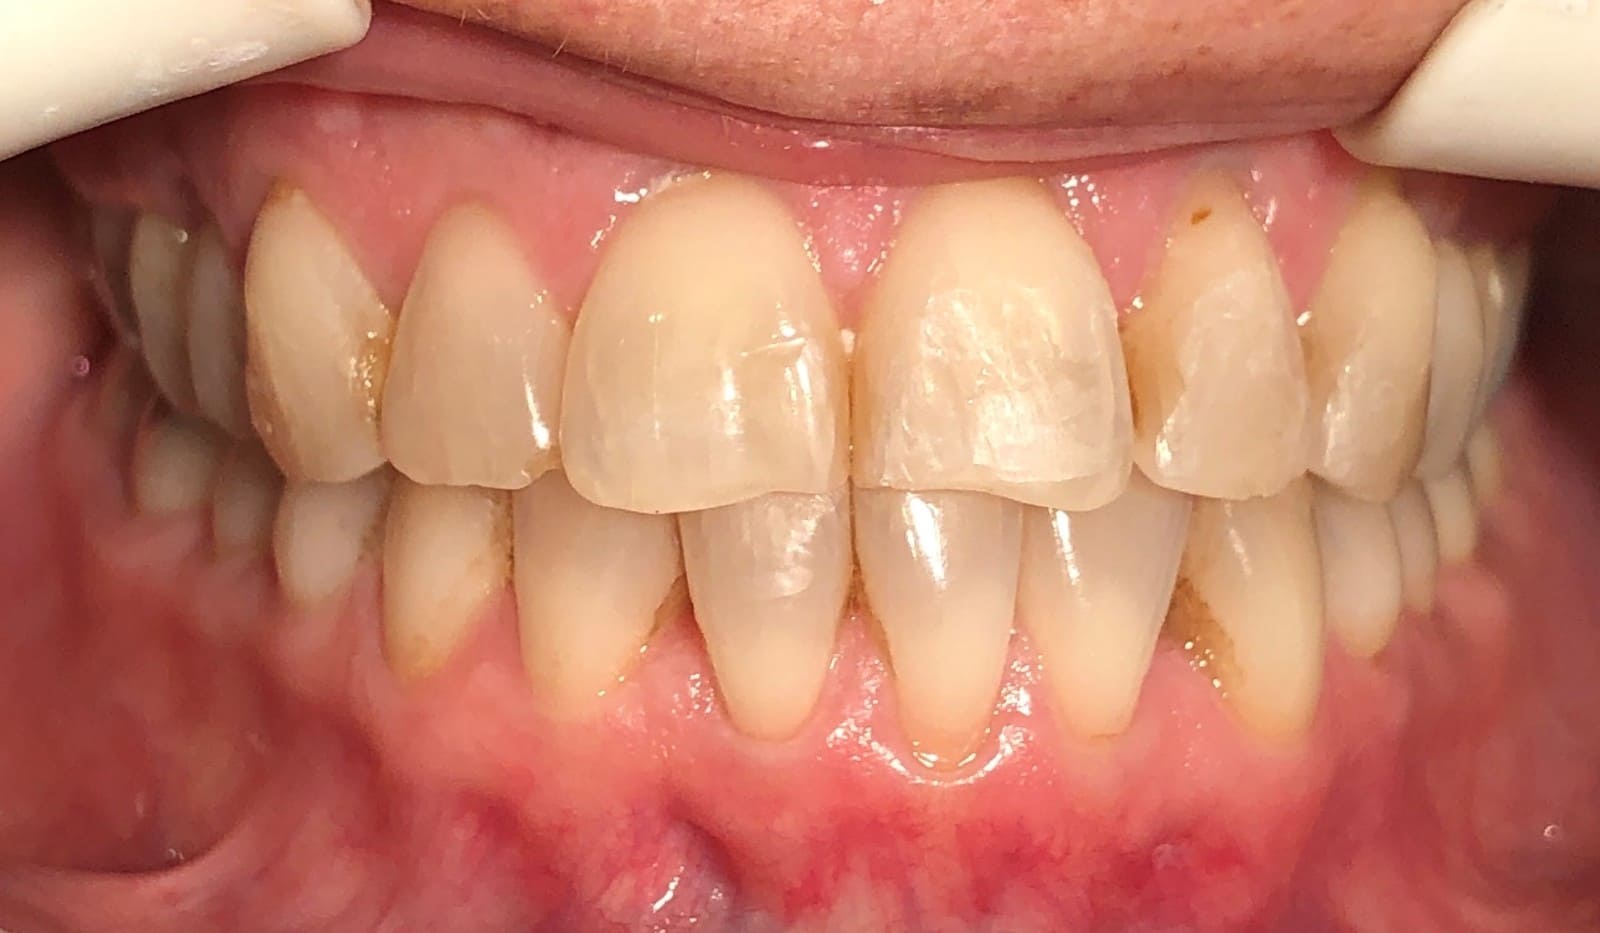

Initial

Final

Results achieved

- Class I relationship achieved

- Functional canine guidance on both sides

- Anterior crossbite corrected

- Normal overjet and overbite achieved

- Midlines coincident

- Proper axial inclination of incisors

- Curve of Spee leveled

- Arches aligned and coordinated

- Arch form improved

- Aesthetic smile line was achieved

- All treatment goals were achieved case